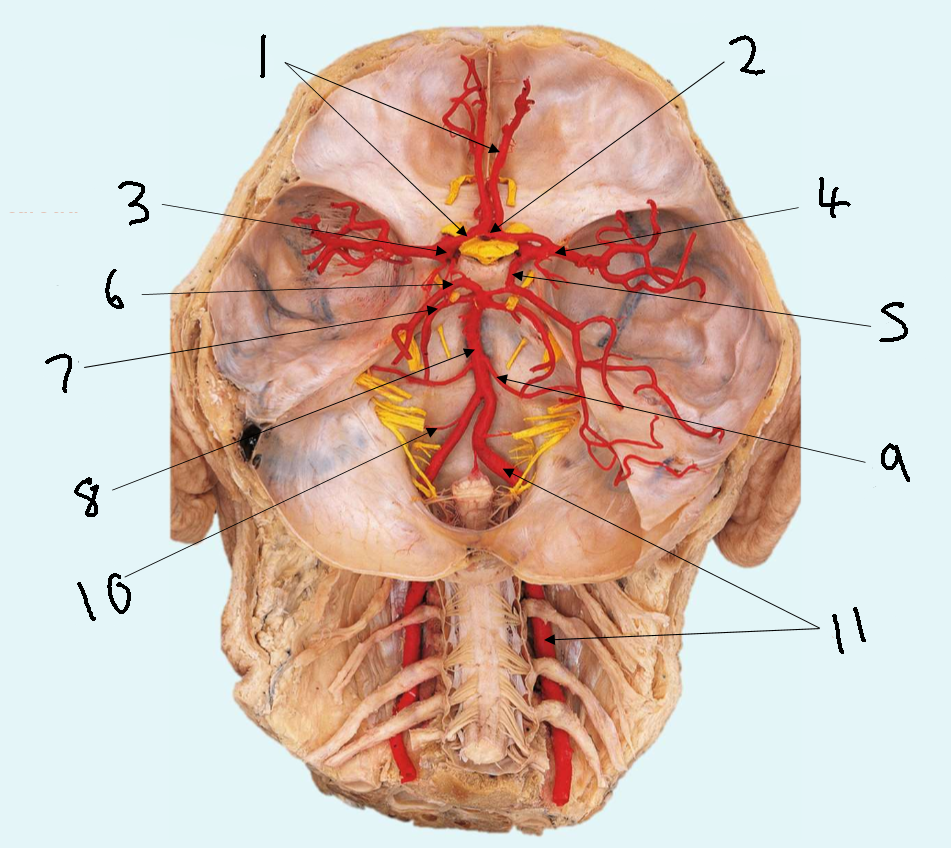

What is 1?

anterior cerebral artery

What is 2?

anterior communicating artery

What is 3?

internal carotid artery

What is 4?

middle cerebral artery

What is 5?

posterior communicating artery

What is 6?

posterior cerebral artery

What is 7?

superior cerebellar artery

What is 8?

basilar artery

What is 9?

anterior inferior cerebellar artery

What is 10?

posterior inferior cerebellar artery

What is 11?

vertebral artery